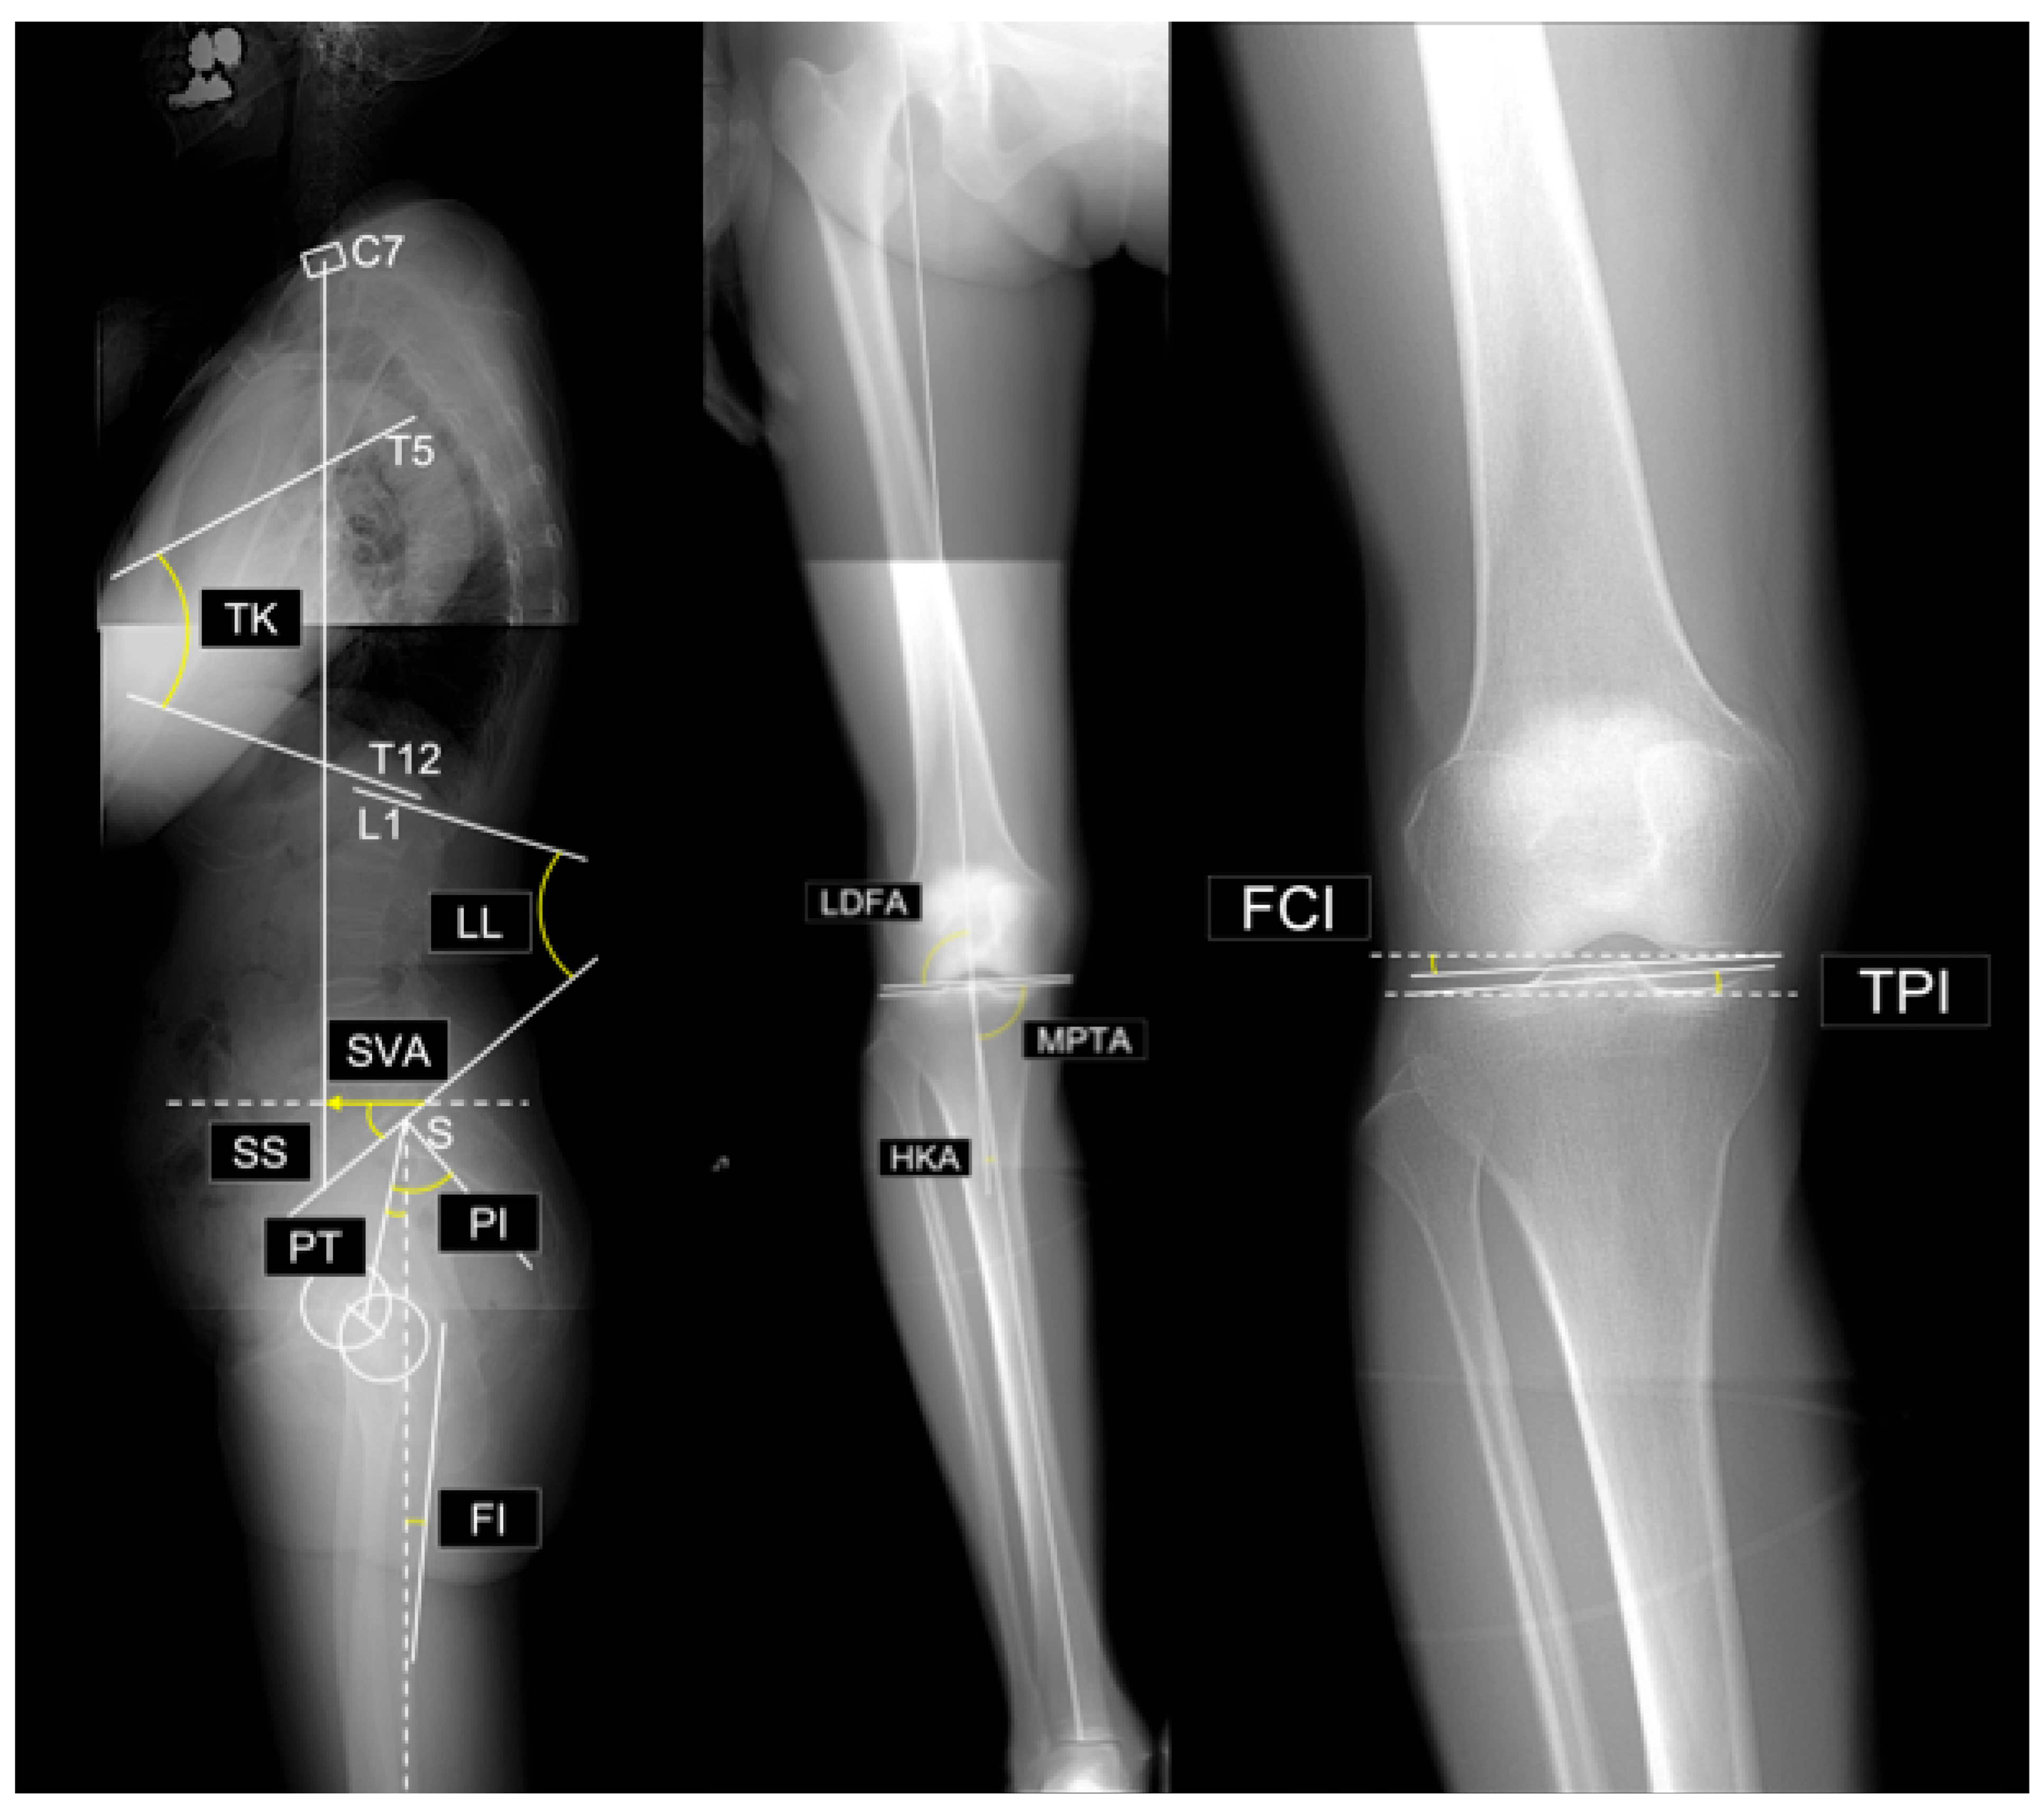

- Sagittal vertical axis (SVA): The horizontal distance between the vertical plumb line dropped from the center of the C7 vertebral body and the posterosuperior corner of the sacrum.

- Thoracic kyphosis (TK): The angle between the superior endplate of T1 and the inferior endplate of T12.

- Lumbar lordosis (LL): The angle between the superior endplate of L1 and the superior endplate of S1.

- Sacral slope (SS): The angle between the superior endplate of S1 and a horizontal reference line.

- Pelvic tilt (PT): The angle between the line connecting the midpoint of the S1 superior endplate to the femoral head center and a vertical reference line

- Pelvic incidence (PI): The angle between a line perpendicular to the S1 superior endplate at its midpoint and the line connecting this midpoint to the femoral head center. By definition, PI = SS + PT.

- PI–LL mismatch: Difference between PI and LL (i.e., PI minus LL).

- Femoral inclination (FI): The angle between the femoral axis and the vertical reference line. Mean values from both sides were used.

- Lateral distal femoral angle (LDFA): The lateral angle between the femoral mechanical axis and distal joint line.

- Medial proximal tibial angle (MPTA): The medial angle between the tibial mechanical axis and proximal joint line.

- Arithmetic hip–knee–ankle angle (aHKA): Defined as MPTA minus LDFA, representing overall lower-limb alignment. Negative values indicate varus alignment.

- Joint line obliquity (JLO): Calculated as the sum of the MPTA and LDFA, reflecting the inclination of the joint line relative to the floor in a bipedal standing position. Values less than 180° indicate the apex distal configuration.

- Hip-knee-ankle angle (HKA): The angle between the mechanical axes of the femur and tibia. A value of 0° represents neutral alignment, and positive values indicate varus alignment.

- Joint line convergence angle (JLCA): The angle formed by the intersection of the distal femoral and proximal tibial joint lines. Positive values indicate a lateral opening.

- Femoral condyle inclination (FCI): The inclination of the femoral joint surface relative to the horizontal plane. Negative values indicate lateral distal inclination.

- Tibial plateau inclination (TPI): inclination of the tibial joint surface relative to the horizontal plane. Negative values indicate medial-distal inclination.